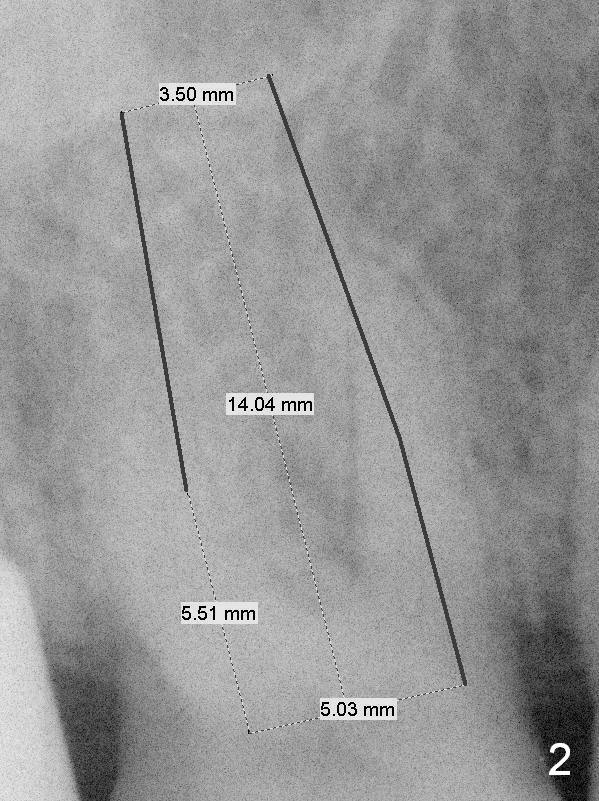

A 67-year-old woman with Parkinson disease has sign of several tooth chip.  The tooth #3 fractures mesiodistally 1 year 7 months post cementation of the crown at #2.  Take photos to show the crack line.  After extraction (Metronidazole), explore the socket to determine bone integrity.  If the septal crest is wide, use 1.6 drill (take 1st PA PRN) and Marking Bur before 4.3 mm Magic Drill.  Otherwise use sequential drills, or alternating with Magic Expander if the bone is soft.  No matter whether IBS (Fig.1) or Tatum (Fig.2) implant is placed, an immediate provisional will be fabricated so that the margin of the provisional is subgingival to prevent buccal plate collapse and bone graft leakage